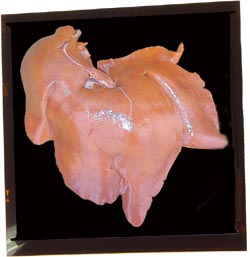

Reins avec des foyers blanchâtres multifocaux

Il s’agit très probablement de néphrite interstitielle. C'est une lésion banale qui est associée à l'infection par le PCV2, mais qui peut avoir d'autres origines.

Atrophie hépatique / hépatomégalie

Conséquence occasionnelle ou très occasionnelle de l'infection par le PCV2 sur des animaux qui développent cliniquement une MAP et qui présentent un ictère, et par conséquent une coloration orangée de la graisse. Cela correspond systématiquement à une inflammation (hépatite) grave du foie.